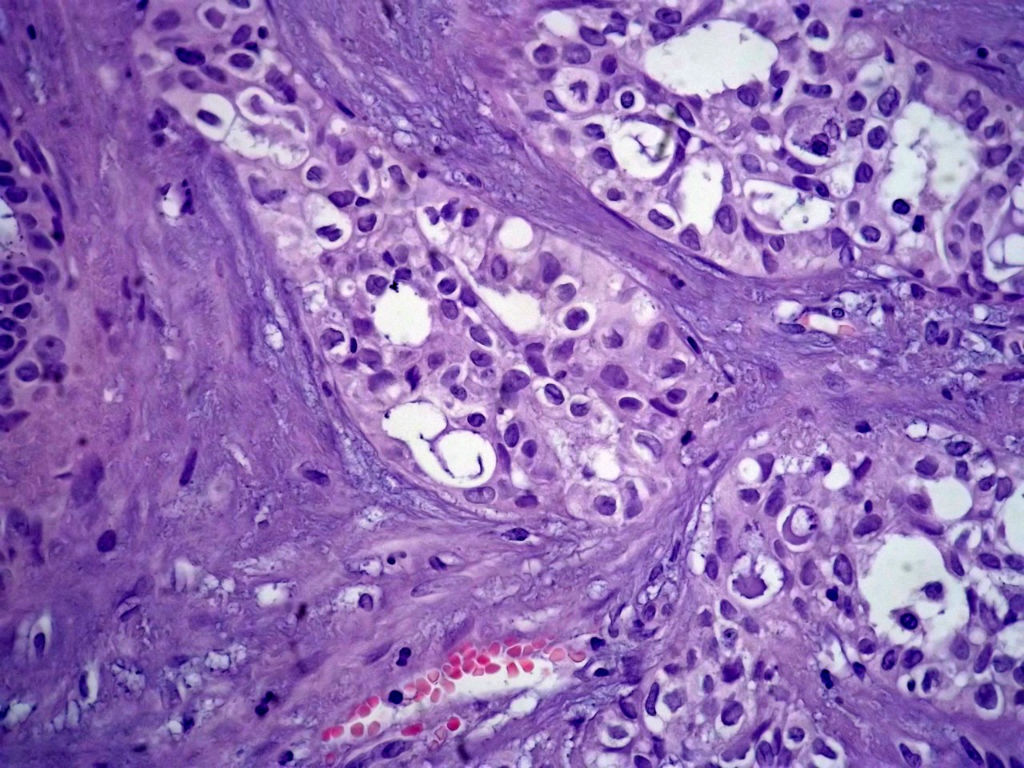

今天的一例术中冰冻。女,49岁,乳腺肿块。人气不旺,换个标题

腺病?癌?其他?(12楼常规,24楼免疫组化及会诊结果)图1

标签:浸润性导管癌 分泌癌 硬化性腺病

乳腺分泌型癌

多谢强版主,这可是俺亲自全程操作的一张片子,俺的一点小经验是“组织要干”,“冷冻要快”,这个病例有点考验俺的神经,发上来听听高手们的意见。大体是乳腺组织一块,切面见一质硬结节,直径2cm,边界欠清,切面灰白色。强版别光夸片子漂亮啊,留下你的高见才放行

导管是乎可见双层上皮,部分上皮增生并有一定异型,考虑硬化性腺病,待石蜡。

导管可见双层上皮,部分上皮增生并有一定异型,考虑硬化性腺病

腺体与腺体之间的对比差异太大,不放心,不除外是癌,如果是我的病例,再次取材冰冻

占楼传常规1-11为冰对。